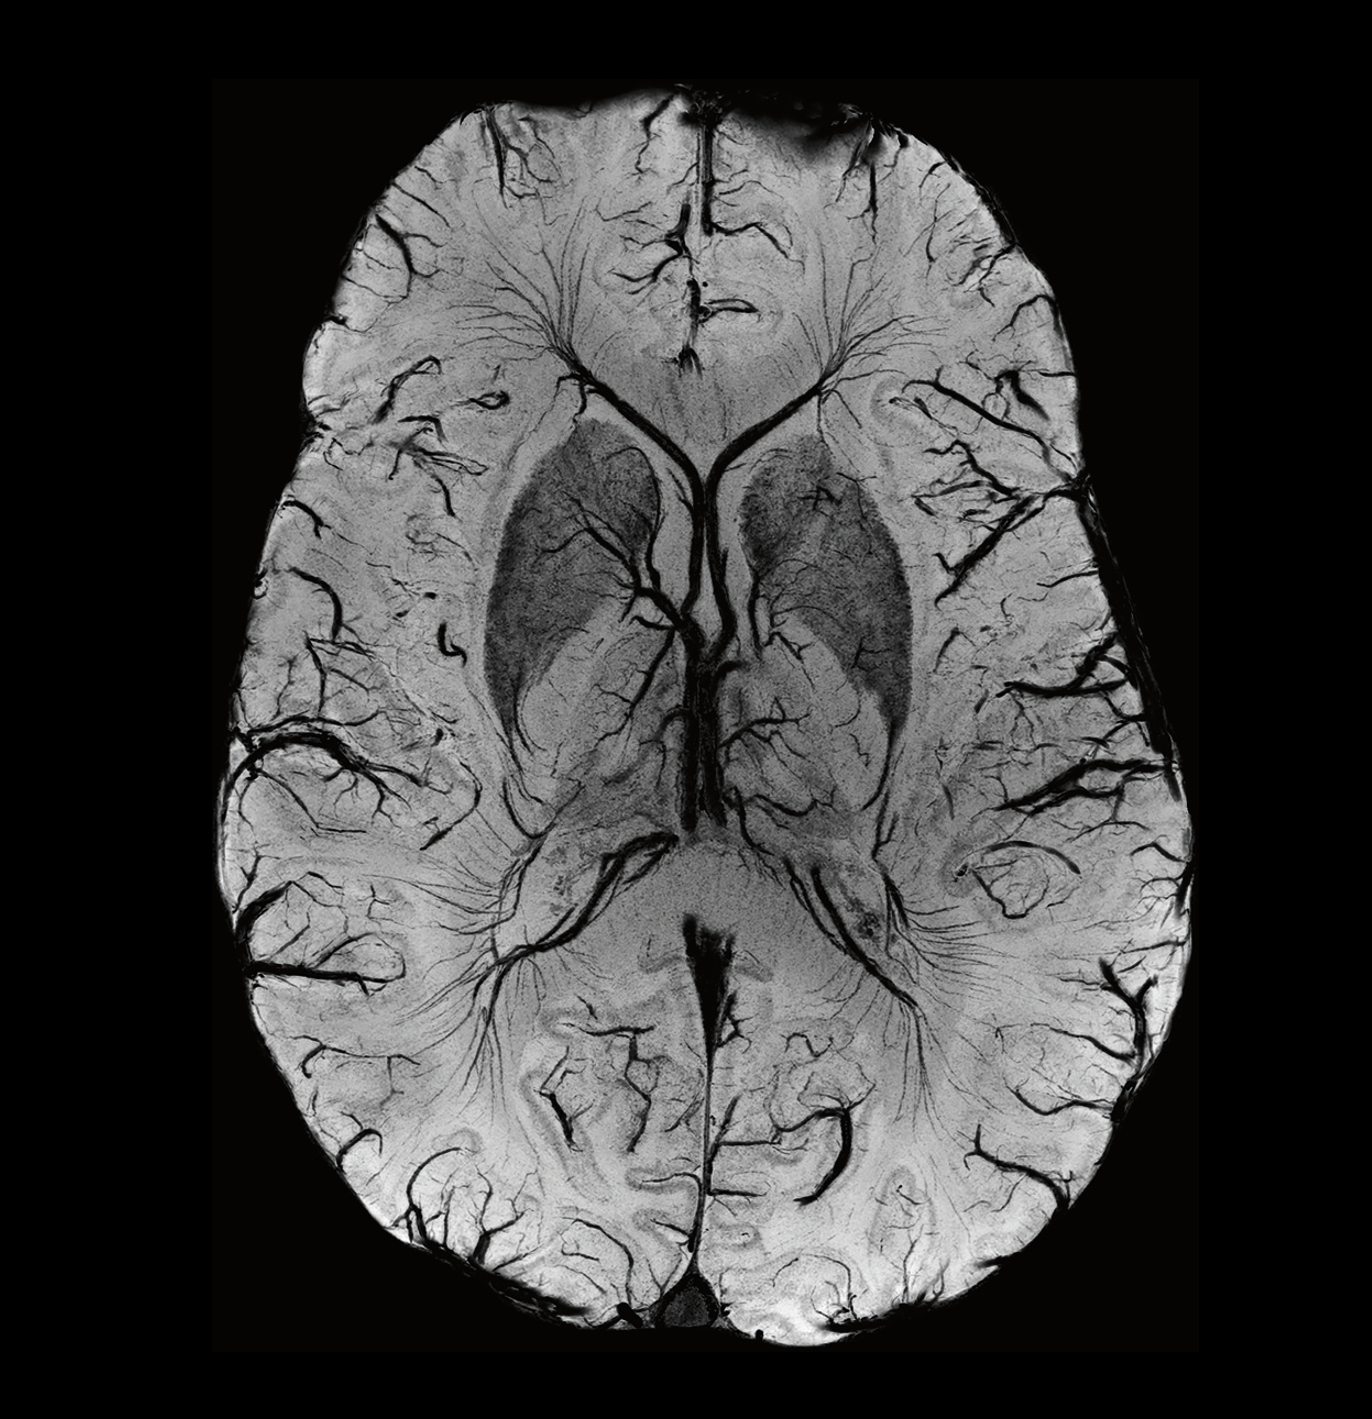

Revolutionary Ultra IQ Technology and Deep Resolve

The Siemens Healthineers MAGNETOM Terra.X is equipped with Ultra IQ Technology, including dynamic pTx, unlocking the full potential of 7T MRI. This revolutionary technology, coupled with Deep Resolve, leads to previously unheard resolution and acquisition speed. Researchers at Campus Biotech can now delve deeper into the intricacies of biological structures, paving the way for groundbreaking discoveries and advancements in medical knowledge.

Open Recon: Fostering Collaboration and Innovation

The deployment of custom reconstruction algorithms is made seamless through Open Recon, a feature that enables the integration of innovative algorithms into clinical workflows. This not only enhances our diagnostic capabilities but also fosters an environment of open and collaborative innovation, positioning Campus Biotech at the forefront of medical imaging research.